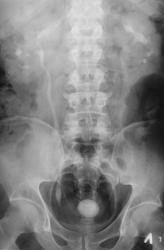

Пациент направлен на обзорную рентгенографию области почек и мочевыводящих путей.

Множественные конкременты МПС: слева в проекции нижней группы, справа скорее всего в средней группе и, конечно, в мочевом пузыре

Самое интересное то, что два дня тому пациенту было сделано УЗИ и было выставлено "объёмное образование мочевого пузыря" (опухоль), а перед этим, что и послужио поводом УЗИ, пациент хорошо "крованул".

Кровить могут и камни, точнее то, что они раздражают. При такой картине явлений всякого рода хронического воспаления-выше крыши, а при УЗИ скорее всего не отдифференцировали стенку пузыря и прилипший камень, но... Иногда на выделительных урограммах прекрасно видные краевые дефекты стенок за счет маленьких стелющихся опухолей, эти кровят будь здоров. Хотя, честно, на этом обзоре стенки четкие, ровные.

Мы, с учетом всего, что насторожило решили начать исследование с пневмоцистографии.

А с чем связано расширение левого мочеточника. Не думаю, что на УЗИ не заметитли камень. Он даёт такую эхотень, при его размерах, что спутать с образованием нельзя. Да и при смене положения должен перемещаться.